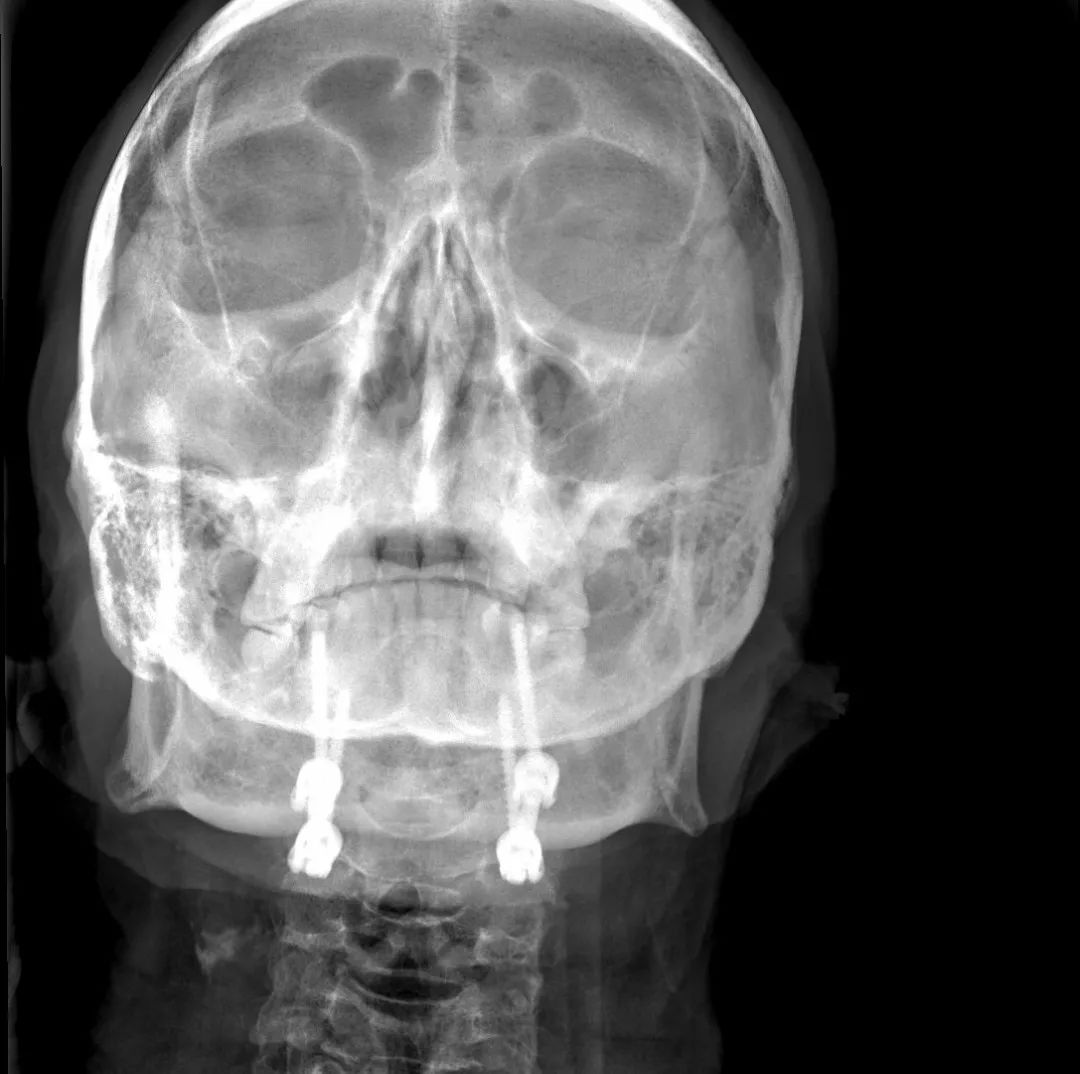

经过全程监护和系统治疗,患者术后恢复良好,骨折解剖复位,复查X线及CT显示固定位置佳,术后3天下地行走,术后4天即出院回家休养。

该手术为我市首例完成C1、2椎弓根钉棒系统固定手术,填补了枣庄在上颈椎外伤手术史上的空白,展现了枣庄市立医院脊柱外科不怕困难、勇于突破、积极向上的精神面貌,也是王存平主任技术高超、胆大心细的具体体现。

枢椎齿状突骨折前路空心螺钉固定术

枢椎齿状突骨折后路Margerl手术

枕颈融合术

颈椎骨折脱位前后联合减压固定术